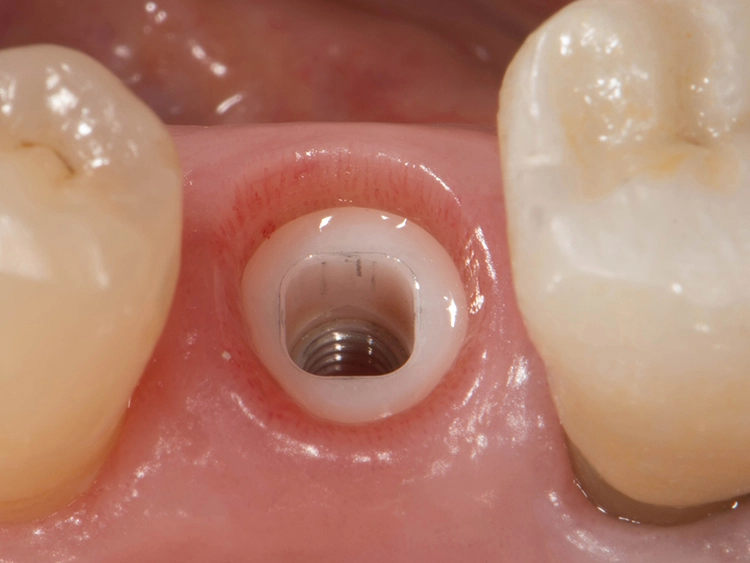

Sie bieten Vorteile, „wenn gleichzeitig eine Knochenaugmentation geplant ist und das Implantat nicht mit einer hohen Primärstabilität inseriert werden kann. Das kann im Frontzahnbereich sein, wenn eine laterale Knochenaugmentation erfolgen soll. Das gilt aber ebenso für den Seitenzahnbereich, wenn gleichzeitig ein Sinuslift durchgeführt wird, wo wir Höhe aufbauen und wir eine unerwartete Überbelastung verhindern wollen“, beschreibt der erfahrene Oralchirurg und erklärt: „Dann sind zweiteilige Implantate einfacher in der Anwendung, weil das Abutment nicht in die Mundhöhle hineinragt und daher eine ungewollte frühzeitige Belastung verhindert werden kann. Außerdem stellen zweiteilige Implantate bei zahnlosen Patienten eine verlässliche Option dar.“

Zweiteilige Implantatsysteme würden darüber hinaus mit einer höheren prothetischen Flexibilität punkten, weil die Aufbauten individueller gestaltet werden können. Dr. Röhling: „Das kann ein Vorteil sein, wenn etwa die prothetische Achse korrigiert werden muss.“ Hinzu kommt, dass bei Anwendung von zweiteiligen Systemen eine Zementierung, die für Fehlerquelle anfällig gesehen wird, entfällt, da sie eine reversibel verschraubte Befestigung erlauben, während bei einteiligen Implantaten die Suprakonstruktion nur zementiert gestaltet werden kann (siehe Fallbeispiel, Abbildungen 1 bis 10).